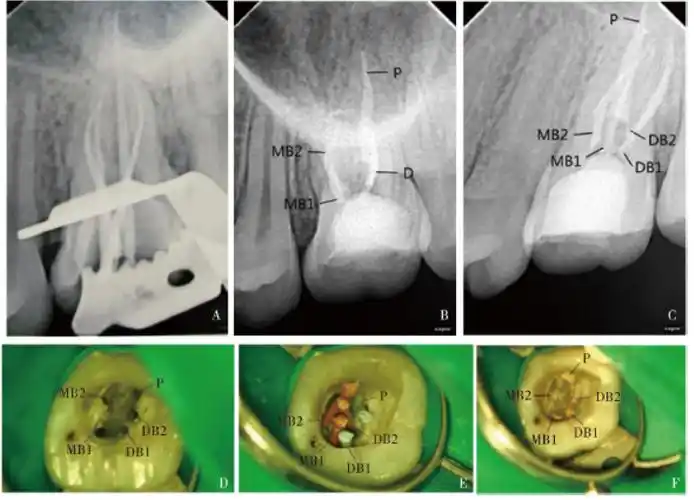

上颌第一磨牙远颊双根管1例